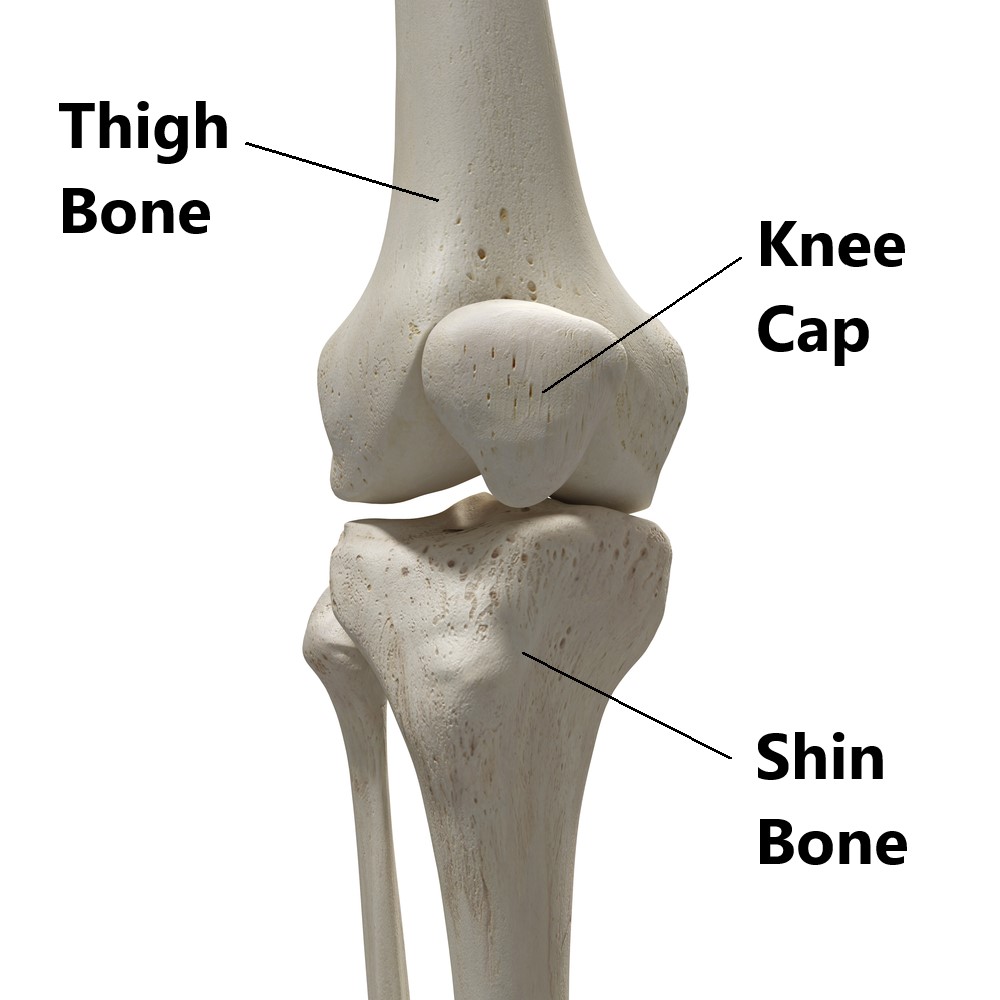

Product Name: Bones in your knee cap discount

Bones in your knee cap discount